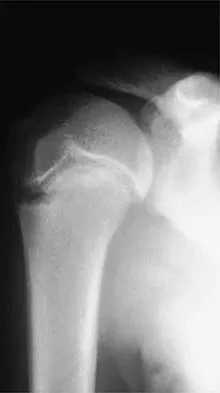

Which of the following findings is seen in the chest radiograph shown in Figure 13?

Orthopaedic surgeons are often responsible for interpreting radiographs of general examinations such as the chest radiograph shown. For accurate interpretation, it is important to systematically review all of the information available on the radiograph. Using this approach, the fracture of the left proximal humerus is readily recognized. Linear air soft-tissue density at the lung periphery would suggest a pneumothorax, but this finding is not shown on the radiograph. The upper thoracic spine is well aligned. The sternoclavicular and distal clavicles are normal.